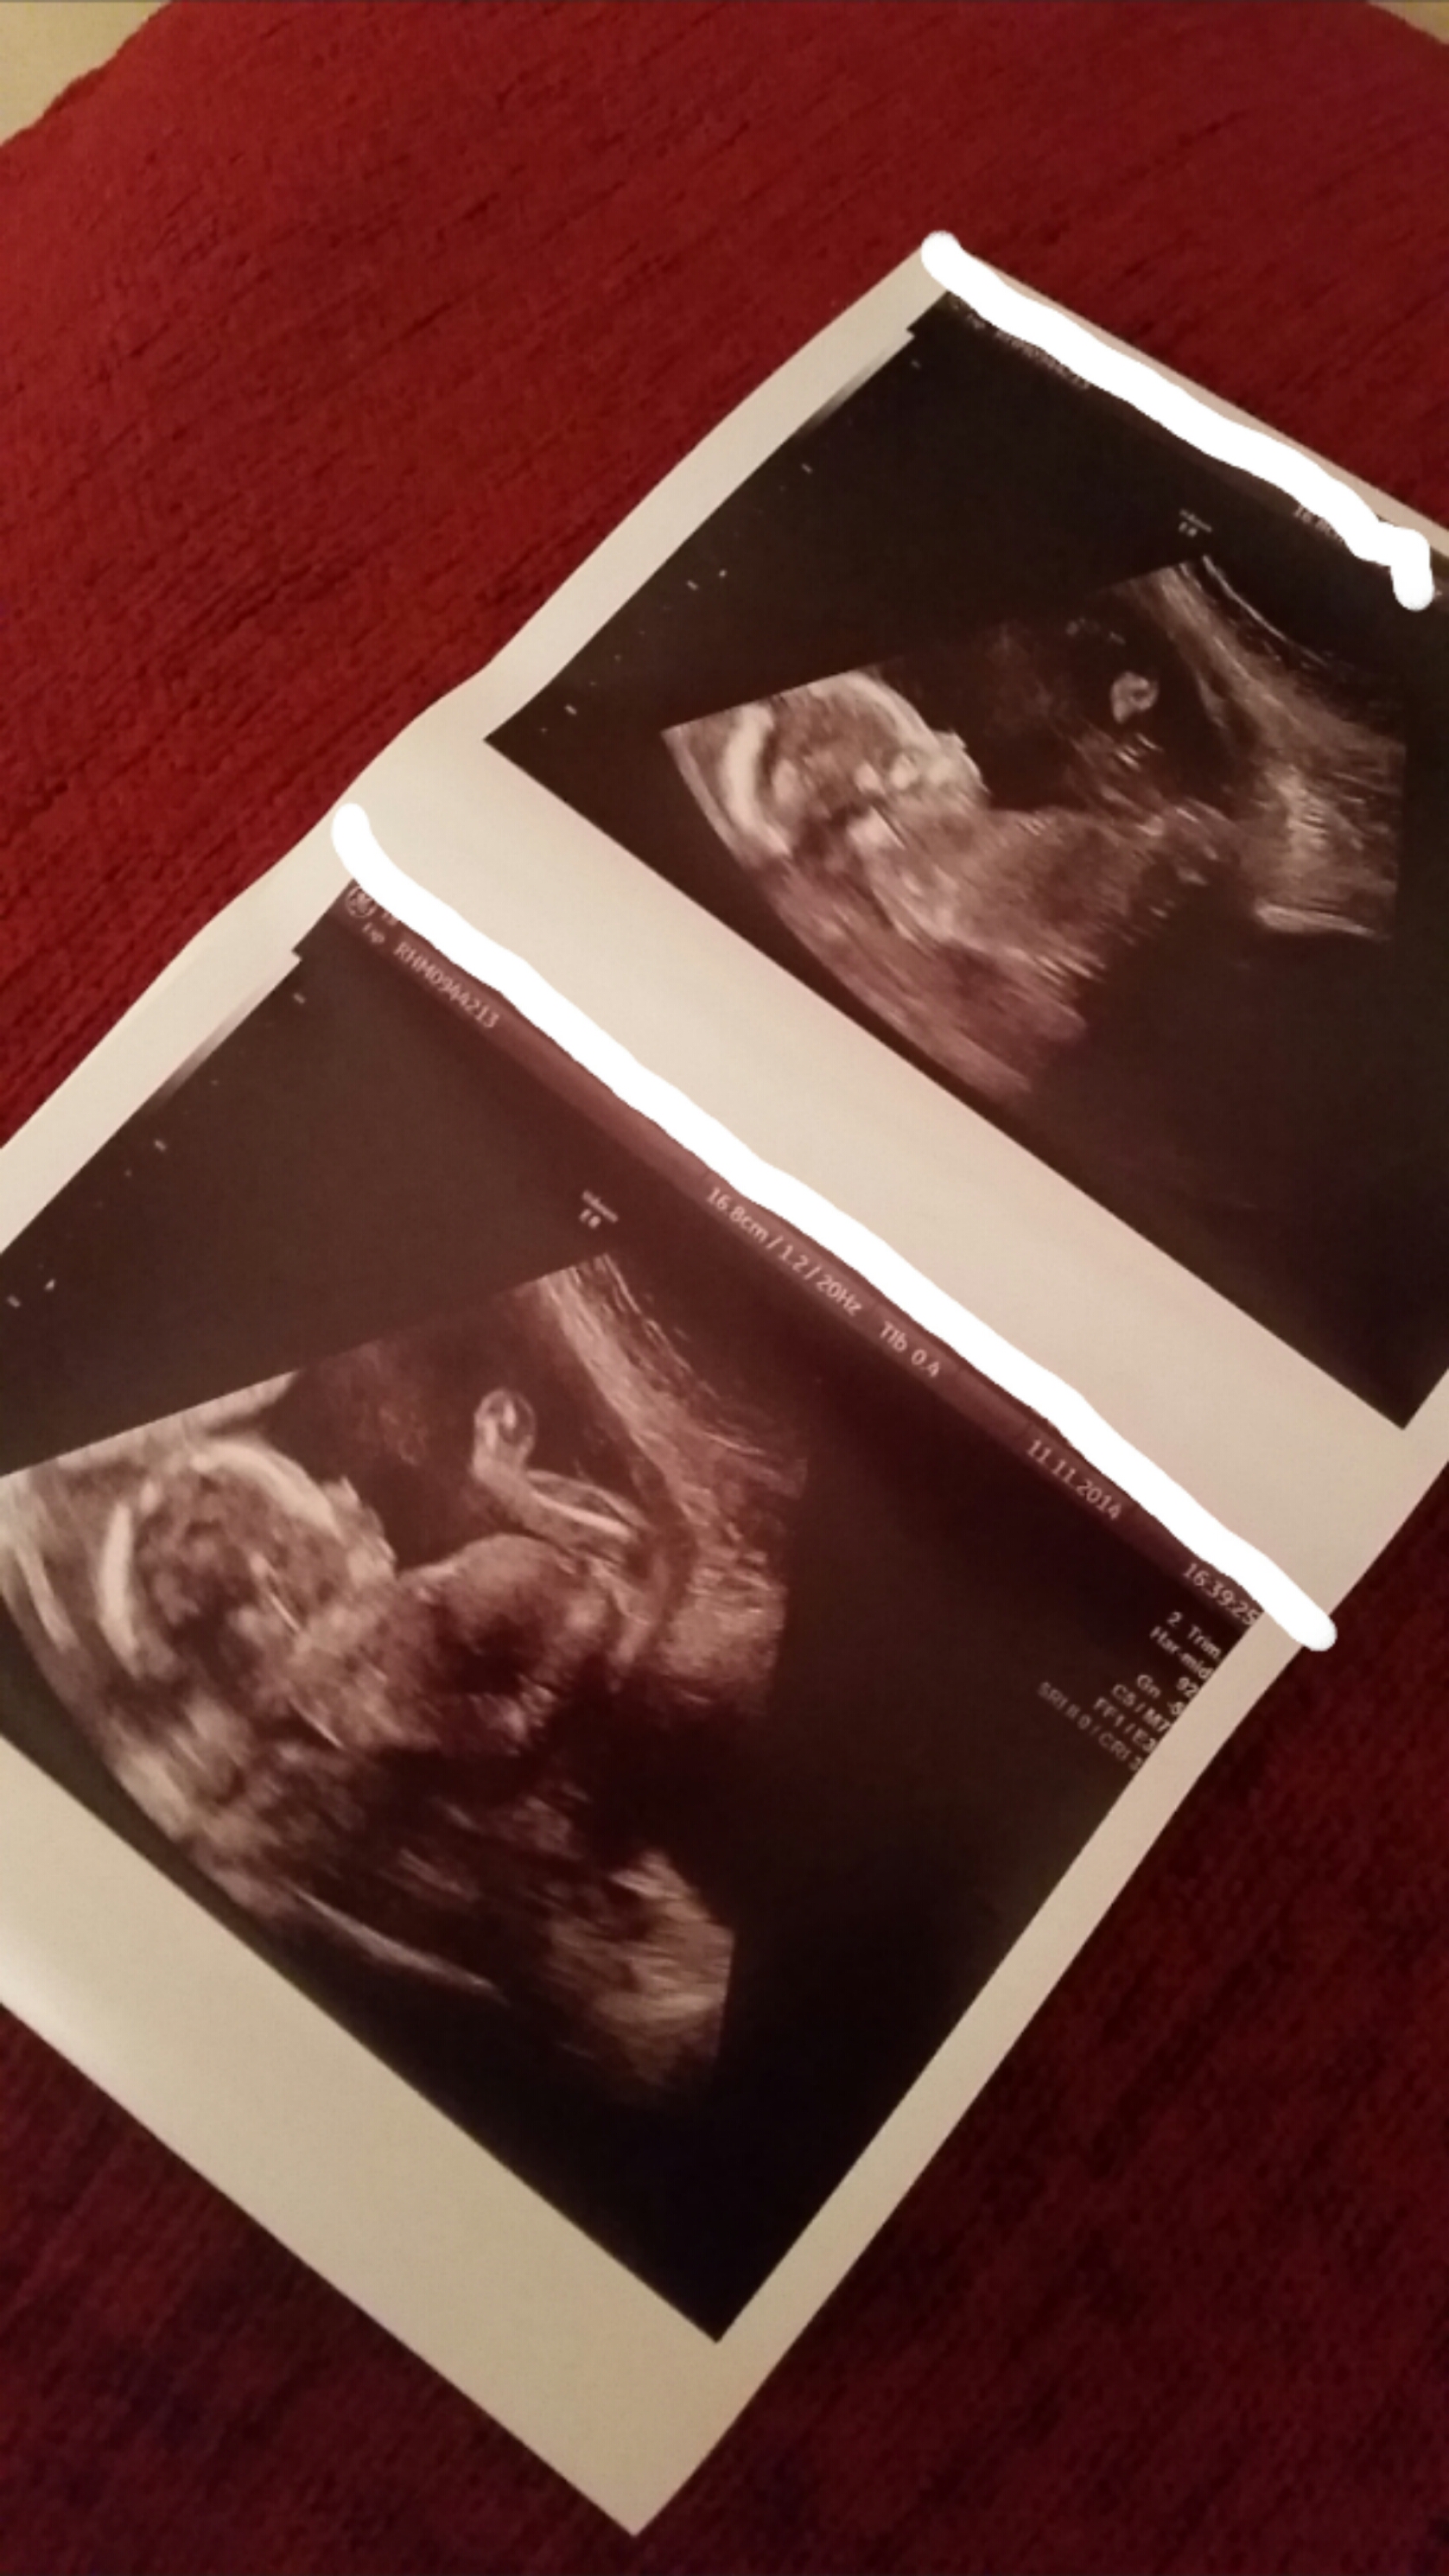

I don't know gender but thinking looks girly from 20 week scan? Any thoughts?

I'm not seeing any obvious 'snail' shape down there which would show little boy parts but I just can't get the detail good enough to be sure I'm afraid:) Any chance of getting the second picture down (bottom picture of the 1st double picture:)) really close up for us and in as much detail as possible??

I think you need a potty shot. I can't see any gender clues in these pics.

I've seen a similar pic on another forum. They too were told girl but it's an odd shot to tell really.